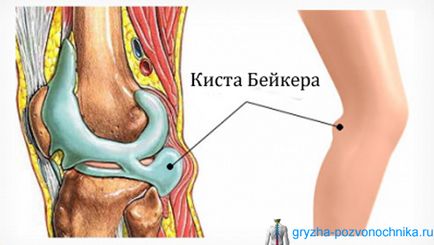

Sérv Becker, amit gyakran Térdhajlati ciszta következtében felmerülő, a gyulladásos folyamatot a térd, és megmutatja a folyadék felhalmozódása a területen alatta.

Az emberi anatómia olyan, hogy a terület a térd szerkezet egy izomcsoport, és azt is, inak, rögzítő őket. Között tendineus zsinórok kialakított tasak, azzal jellemezve, a gyulladás során ott kezd felhalmozódni folyadék további fejlesztése, megjelenéséhez vezet ödéma, amely az úgynevezett sérv Becker.

A kezdeti szakaszban a betegség, sérv miatt érezhető kellemetlen érzés a térd. De, a növekedés, hogy kezd befolyásolja az idegek, és a beteg kezdi érezni, zsibbadás és bizsergés, lassan áramló nagy fájdalom.

Egy tipikus megnyilvánulása egy sérv Becker a képtelenség, hogy teljes mértékben hajlik a lábát.

Emellett megkezdődik módosított és megjelenése popliteához terület, úgy tűnik, rugalmas formáció, nagyon hasonlít a daganat. A legsúlyosabb esetekben a Becker sérv vezet trombózis vénák. Abban az esetben, shell szakadás, a beteg úgy érzi, fájdalom, és a testhőmérséklet lesz nagyon magas.